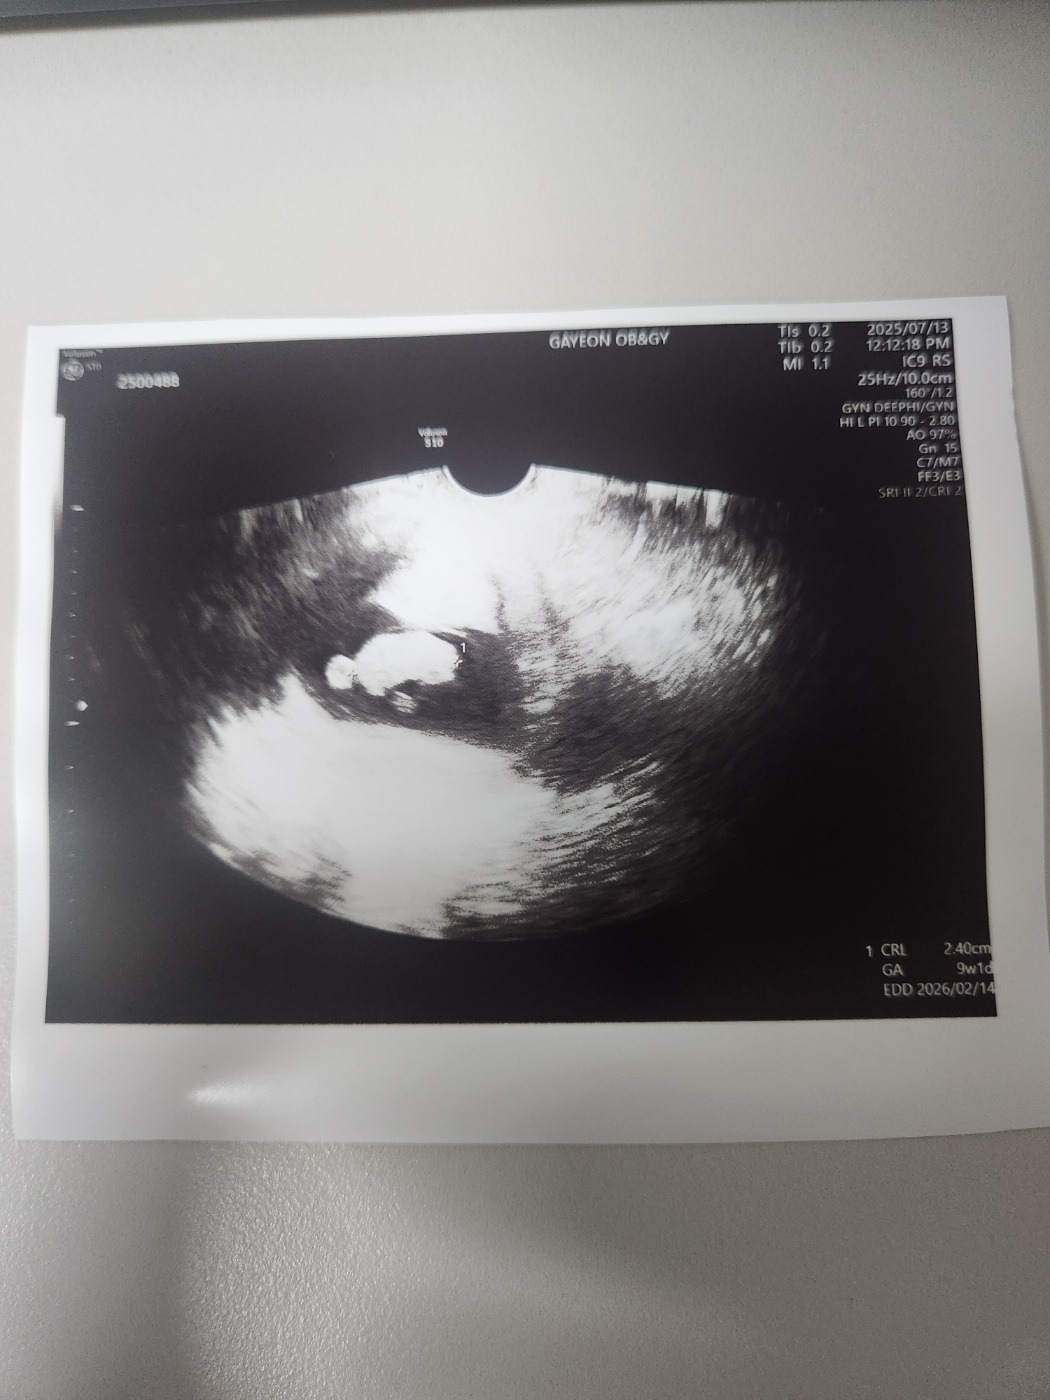

임신 9주 차 (9주 1일 차) 초음파 젤리곰 난황 확인에 대해서 알려드리겠습니다.

그새 9주 차가 되니 아기는 훌쩍 커있었습니다.

팔다리가 나와서 젤리곰처럼 초음파로 보인다고 했습니다.

다른 사람들은 젤리곰처럼 잘 보이던데, 저는 딱히 그렇게 보이진 않는 것 같았습니다.

젤리곰 같이 생긴 태아 옆에 동그랗게 난황도 있습니다.